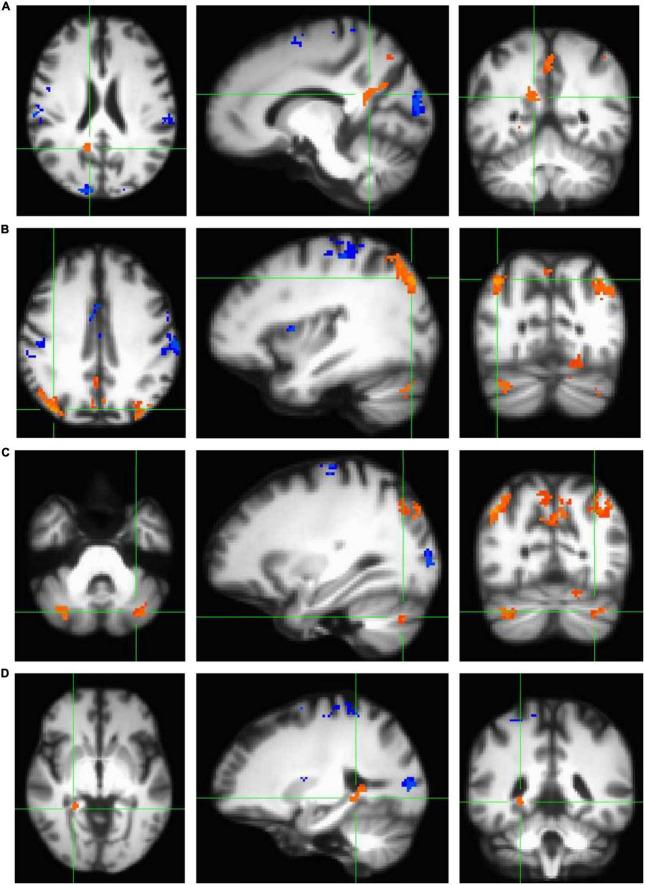

Spatial navigation is a cognitive skill critical for accomplishing daily goal-directed behavior in a complex environment; however, older adults exhibit marked decline in navigation performance with age. Neuroprotective interventions that enhance the functional integrity of navigation-linked brain regions, such as those in the medial temporal lobe memory system, may preserve spatial navigation performance in older adults. Importantly, a well-established body of literature suggests that cardiorespiratory fitness has measurable effects on neurobiological integrity in the medial temporal lobes, as well as in other brain areas implicated in spatial navigation, such as the precuneus and cerebellum. However, whether cardiorespiratory fitness modulates brain activity in these regions during navigation in older adults remains unknown. Thus, the primary objective of the current study was to examine cardiorespiratory fitness as a modulator of fMRI activity in navigation-linked brain regions in cognitively healthy older adults. To accomplish this objective, cognitively intact participants ( = 22, aged 60-80 years) underwent cardiorespiratory fitness testing to estimate maximal oxygen uptake ( O) and underwent whole-brain high-resolution fMRI while performing a virtual reality navigation task. Our older adult sample demonstrated significant fMRI signal in the right and left retrosplenial cortex, right precuneus, right and left inferior parietal cortex, right and left cerebellum lobule VIIa Crus I and II, right fusiform gyrus, right parahippocampal cortex, right lingual gyrus, and right hippocampus during encoding of a virtual environment. Most importantly, in women but not men ( = 16), cardiorespiratory fitness was positively associated with fMRI activity in the right cerebellum lobule VIIa Crus I and II, but not other navigation-linked brain areas. These findings suggest that the influence of cardiorespiratory fitness on brain function extends beyond the hippocampus, as observed in other work, to the cerebellum lobule VIIa Crus I and II, a component of the cerebellum that has recently been linked to cognition and more specifically, spatial processing.

空间导航是一种认知技能,对于在复杂环境中完成日常目标导向行为至关重要;然而,老年人的导航能力会随着年龄增长而显著下降。神经保护干预措施可增强与导航相关的脑区(如内侧颞叶记忆系统中的脑区)的功能完整性,这可能会保留老年人的空间导航能力。重要的是,大量已确立的文献表明,心肺适能对内侧颞叶以及其他与空间导航相关的脑区(如楔前叶和小脑)的神经生物学完整性有可测量的影响。然而,心肺适能是否会在老年人导航过程中调节这些区域的大脑活动仍不清楚。因此,本研究的主要目的是检验心肺适能作为认知健康的老年人中与导航相关的脑区功能磁共振成像(fMRI)活动调节因素的作用。为实现这一目标,认知功能完好的参与者(n = 22,年龄在60 - 80岁之间)接受了心肺适能测试以估计最大摄氧量(VO₂),并在执行虚拟现实导航任务时接受了全脑高分辨率fMRI检查。我们的老年样本在虚拟环境编码过程中,右侧和左侧压后皮质、右侧楔前叶、右侧和左侧顶下小叶、右侧和左侧小脑小叶VIIa Crus I和II、右侧梭状回、右侧海马旁皮质、右侧舌回和右侧海马中显示出显著的fMRI信号。最重要的是,在女性(n = 16)而非男性中,心肺适能与右侧小脑小叶VIIa Crus I和II的fMRI活动呈正相关,但与其他与导航相关的脑区无关。这些发现表明,心肺适能对脑功能的影响不仅像其他研究中观察到的那样扩展到海马体,还延伸到小脑小叶VIIa Crus I和II,这是小脑的一个组成部分,最近已被证明与认知,尤其是空间处理有关。